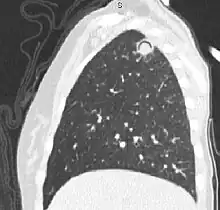

Sagittal reformat from a CT scan of the chest showing air crescent sign in a patient with invasive fungal infection. There is a rounded cavity in the apical right upper lobe, with a non-dependant soft-tissue nodule within it. Also there is some subtle ground-glass opacity surrounding the lesion.